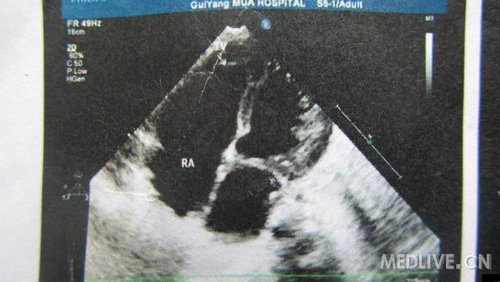

患儿,女,6月,足月剖腹产,出生后家长发现喘憋,未重视。现症状加重,不能喂食而就诊!

片子列出,急盼高手指点,不知生存几率有几分?